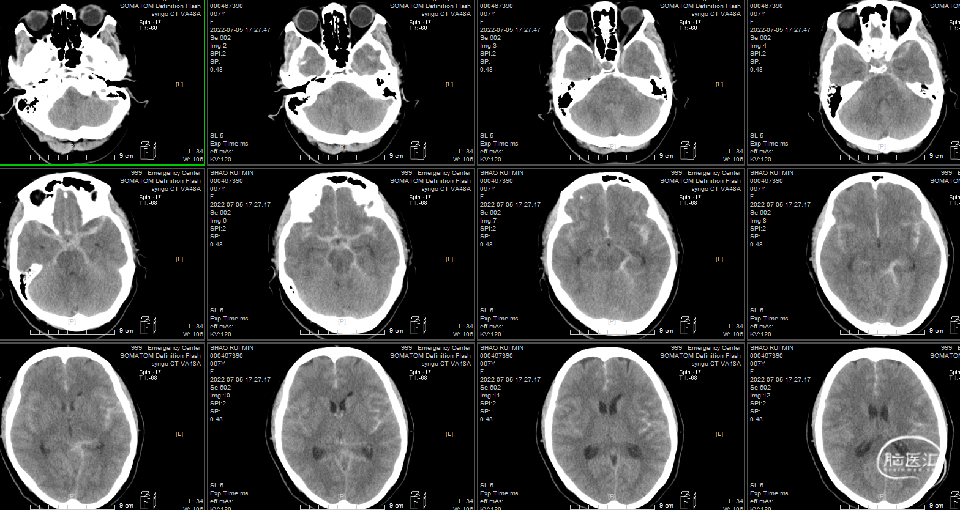

头颅CT(平扫)、胸部CT(平扫)第一次:

1、自发蛛网膜下腔出血,建议CTA检查。

急诊头颅CT:自发蛛网膜下腔出血。